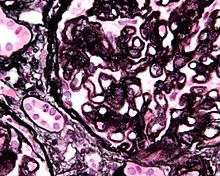

Additional images

-

Renal corpuscle. GBM is #1.